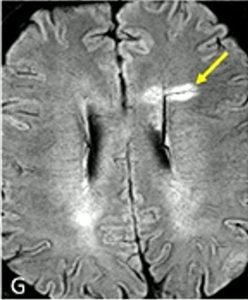

Central Vein Sign (CVS) Lesion

A concept that may be new to patients is the central vein sign (CVS) lesion. With the higher power MRIs that are available in research today, the 7T machine, we can see if a lesion has developed around a vein running through the middle. Hence the name, central vein sign. More than 50% of patients with MS will have this type of lesion.

Once these were identified on the stronger MRI machines, a protocol was developed to help see them in lower power machines used in clinical care. If a patient has 6 or more CVS lesions (called select 6), that can be used as one more vote toward confirmation of MS. This is especially helpful in patients who may have lesions due to other causes such as vascular conditions because those lesions do not form around a vein in this way. CVS lesions are not required to make a diagnosis of MS, they can only help confirm it. Most clinical MRIs don’t quantify CVS yet, but it may become more common as these new criteria become accepted.